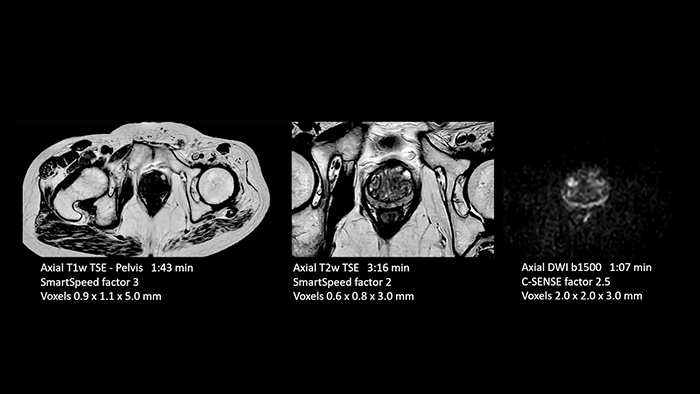

Dr. Schröter points out that a more confident diagnosis requires high-quality images with more diagnostic information. “Philips SmartSpeed provided that to us. AI denoises the clinical images without losing any important data, resulting in high-resolution images. It keeps all the information we need and makes the images better. We can apply SmartSpeed to almost all sequences. That is a big step forward! We use it for example in 3D imaging and in diffusion-weighted imaging, to dramatically reduce scan time or increase image resolution, which is quite useful. There are small lesions that we would certainly have seen without SmartSpeed, however it would have taken us longer to properly diagnose. In 3D MSK images with extremely high resolution, we uncover the finest anatomical structures and can thus report very detailed findings.”

In our prostate exams we have saved almost 50 percent of time and obtain significantly higher resolution.”

- Prostate

With SmartSpeed also scan times for diffusion imaging and motion-free imaging can be reduced. Scanned without contrast agent. Performed with 1.5T Ambition X, dS Torso coil.

- Prostate

With SmartSpeed also scan times for diffusion imaging and motion-free imaging can be reduced. Scanned without contrast agent. Performed with 1.5T Ambition X, dS Torso coil.